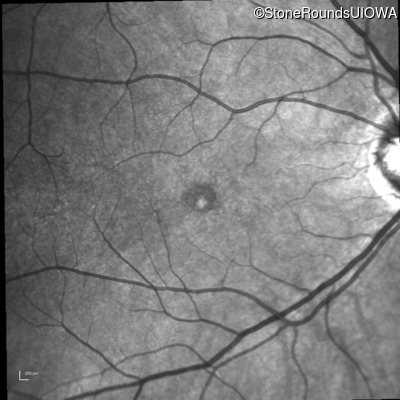

Fluorescein Angiography - Right - 20/20 -1

Exemplar